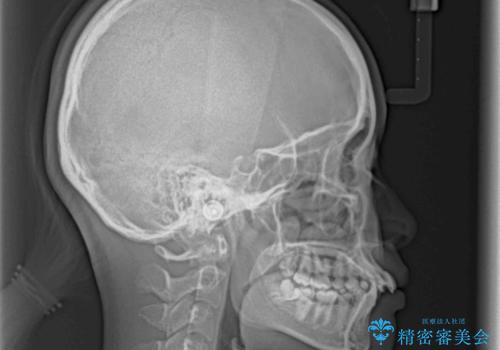

- 前に傾斜して飛び出した上顎前歯を気にして来院された患者様です。

上下前歯の前後差が大きく、下顎前歯が隠れるほど深い咬合で、咬合力が強い状態でした。

口元の突出感を改善するために、上下左右の第一小臼歯4本を抜歯し、ワイヤー装置にて矯正治療を行うこととしました。

深い咬み合わせの改善に時間がかかりましたが、下顎前歯がしっかりと見えるまでに整えることができ、口元の突出感も大幅に改善することができました。